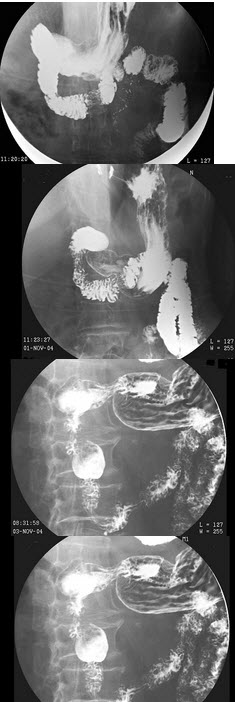

21、判断题 慢性化脓性骨髓炎一般无或仅有轻微的不规则骨质破坏,一般无死骨形成。

女,74岁,上腹痛4月,纳差,结合图像,最可能的诊断为()